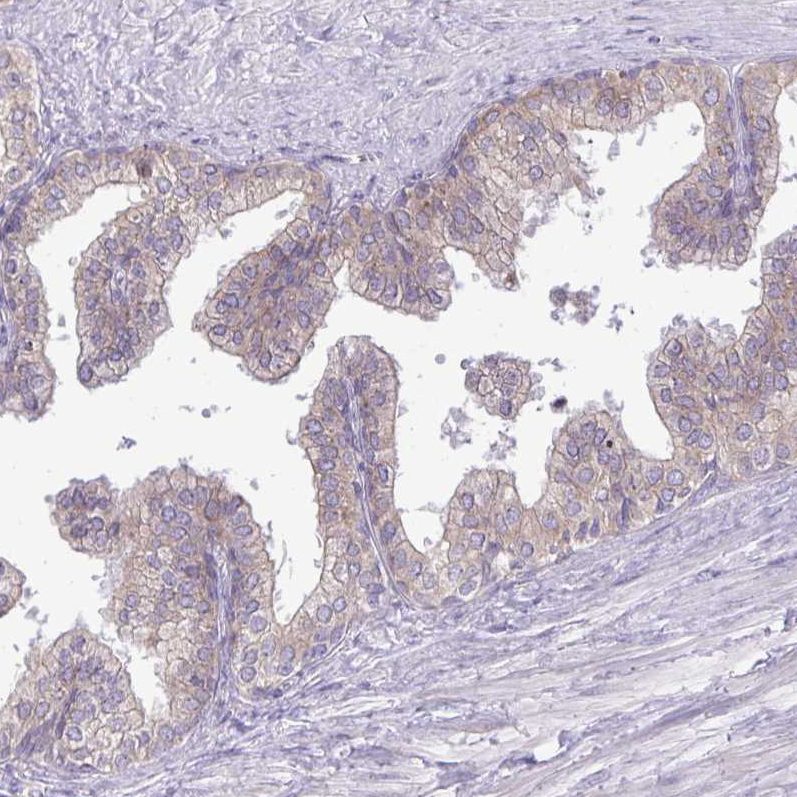

Immunohistochemical staining of human kidney shows moderate cytoplasmic positivity in cells in tubules.